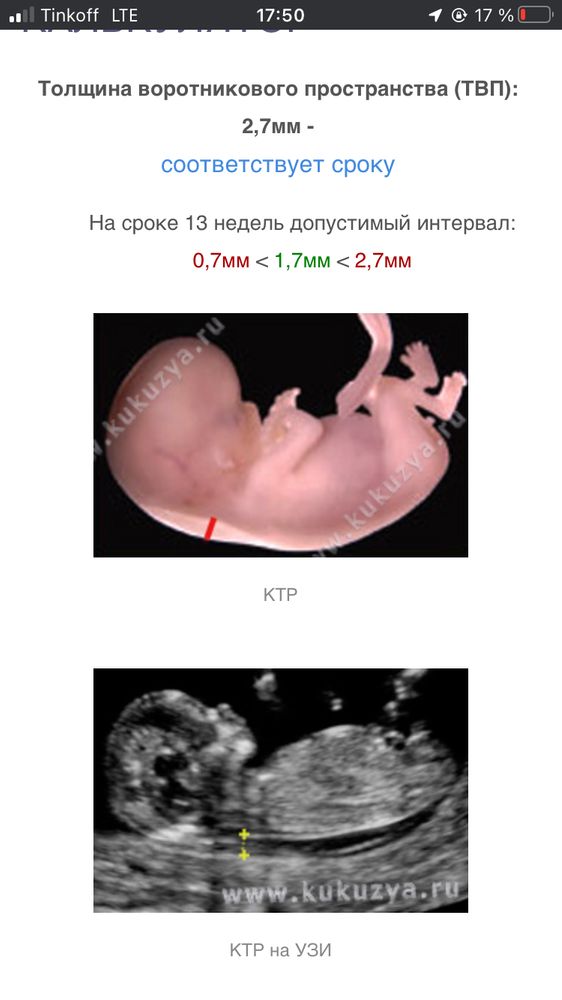

Ну по первому скринингу немного ТВП завышен и риск по трисомии 21 не самый низкий. Думаю, что все в порядке, но НИПТ точно не лишний. Пусть все обойдется и лялька родится здоровым❤️🤞🏼

Темная Лошадка, для 13 недель норма ТВП - до 3. Так что никуда он не завышен)

Темная Лошадка, так смотря какой срок) до 2,3 это для 10,11 недели порог

Юлия, в Канаде вообще до 4 норма. Мне 2 врача объясняли, что идеально до 2. А после 2.3 могут быть проблемы. И не обязательно хромосомные